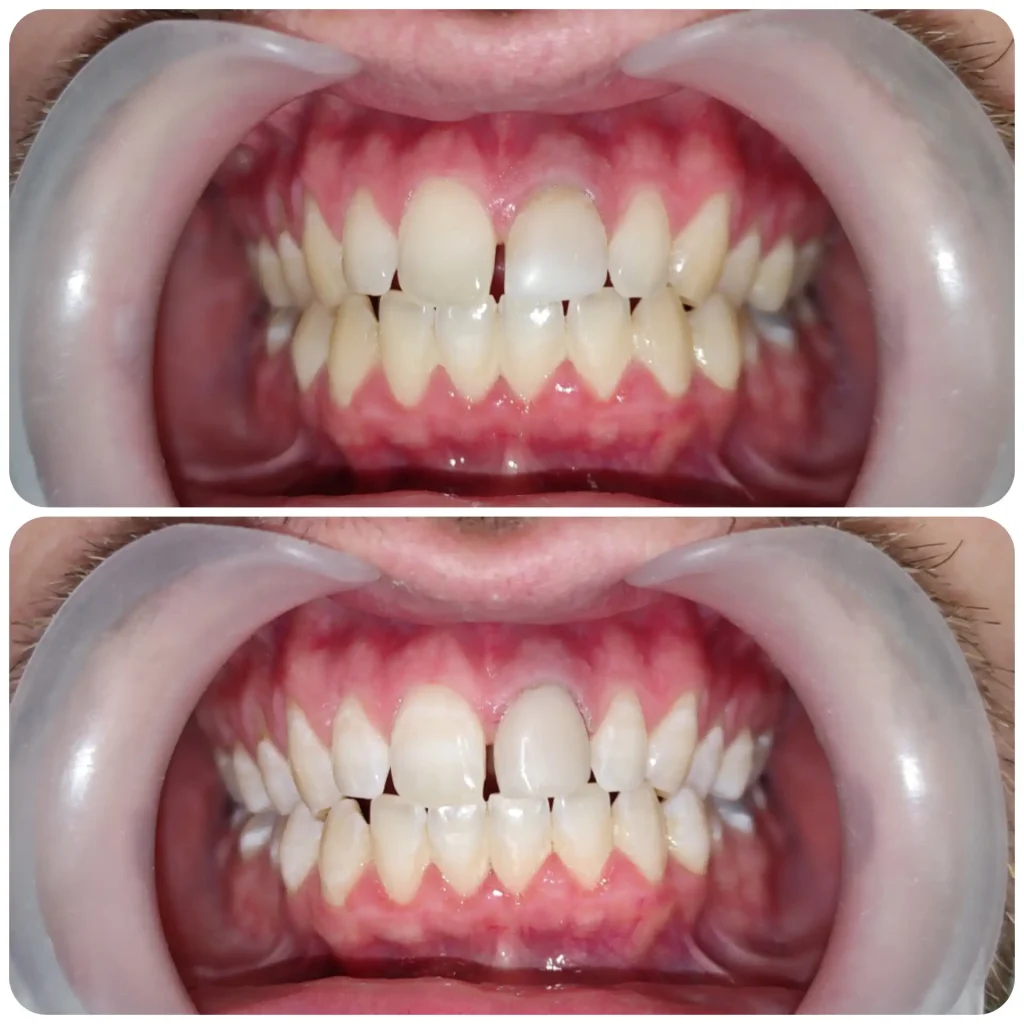

Esztétikai és fogmegtartó kezelések mellett nagy érdeklődéssel fordulok a fogszabályozás szakirány felé. Jelenleg fogszabályozási rezidensként sajátíthatom és mélyíthetem el tudásomat a harmonikus és funkcionálisan megfelelő harapás és esztétikai megjelenés kialakításában.

Szeretem felhívni a pácienseim figyelmét arra. hogy mekkora fontossággal bír egy megfelelően elvégzett fogszabályozási kezelés.